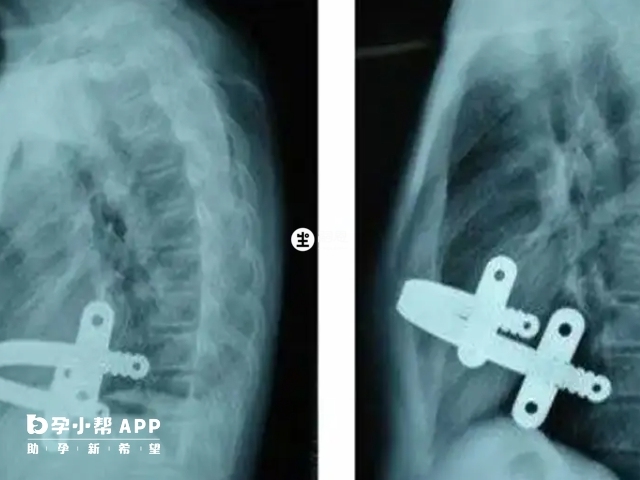

轻度鸡胸:主要表现于漏斗胸、肋软骨及部分肋骨向背侧凹陷畸形,形成漏斗状,一般没有什么明显的症状,不过有部分患者很容易在幼儿时期出现反复性感冒和呼吸道感染的情况,随着病情的加重还会出现体力下降,胸闷气短、呼吸困难等症状,这主要是心肺组织受压、心排血量减少所致。

重度鸡胸:会出现胸廓前凸畸形、胸廓前后径加长和驼背,导致呼吸幅度减弱,肺组织弹性减弱,产生气促、乏力等症状。如果说不及时治疗的话,很可能会患上哮喘的情况,还会导致活动耐力差,易疲劳,并带来一定的精神和心理负担。

对于轻型的,可以咨询专科医生,决定是否进一步治疗。严重者,要去正规的医院,接受专业全面的治疗,必要时进行相关矫正手术。而目前临床上面关于鸡胸的治疗方法是有4种的。